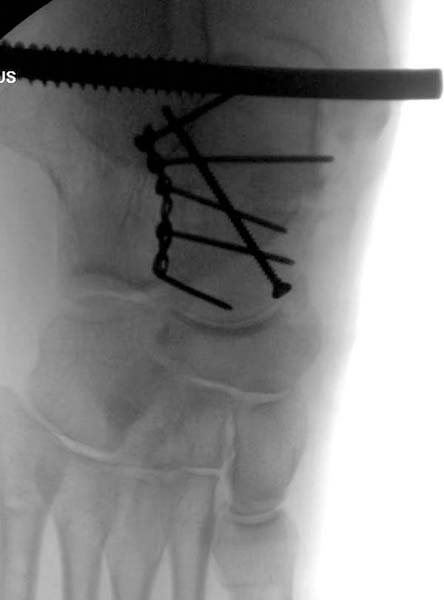

По характеру повреждения головка находится сзади и напрашивается задний Кохер-Лангенбек доступ, но в заднем доступе имеется риск повреждения магистрального кровоснабжения головки a. circumflexa. Более щадящая trochanteric flip (digastric osteotomy) сохранит кровоснабжение и дасть возможность работу при вывихнутом суставе.

После спадения отека на стопе произведена фиксация тарана. Кстати, коллеги пересмотрели первоначальную консультацию по позвоночнику и на двух уровнях провели фиксацию. Из-за длительного постельного режима без нагрузки таз не стали оперировать...